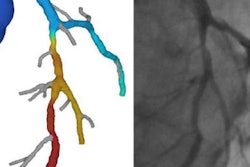

The Heartflow software used by Nieman's group in Rotterdam makes a lot of calculations, and ultimately displays the coronaries in a colorful 3D tree where blue indicates patent arteries and orange and yellow reveal hemodynamic obstruction.

Coronary CT angiography revealed stenosis > 50% in a mid-40s man with atrial fibrillation. However, FFR-CT showed no flow restrictions (depicted in blue) in the area surrounding the calcifications, only minor flow restrictions (yellow and red) in the distal arteries, enabling the patient to be managed conservatively. Image courtesy of Dr. Koen Nieman."This patient would be very easy to send to the cath lab, and most people would do that or more -- but the interesting thing was that FFR-CT as calculated did not find any significant drop in FFR over the lesions," Nieman said. As a result, the patient could be managed conservatively.

In patients such as these who have plaque and calcium in the arteries, peripheral lesions often show FFR-CT values below 0.08, indicating hemodynamic significance in the small vessels. But FFR-CT readings fall to normal levels around the lesion (FFR 0.97 to 0.83 in this case), clearing the way for noninvasive management with medication, Nieman said.